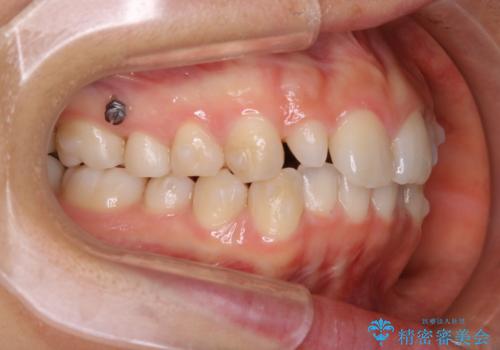

- 上の前歯が大きい事と下の前歯のがたつきを気にされてご相談にいらした方です。上の2番目の歯が矮小歯であったため、矯正治療にて歯のスペースを作った後、矮小歯には被せ物をして前歯のバランスを整えました。

歯科技工士さんとの打ち合わせを重ね、周囲の歯としっかりなじむ天然歯のような被せ物をお作りすることが出来ました。

矯正治療と補綴治療をうまく組み合わせることで、美しい口元に仕上げることが出来ました。矯正治療、補綴治療をまとめて行える総合歯科治療を体現した治療といえます。